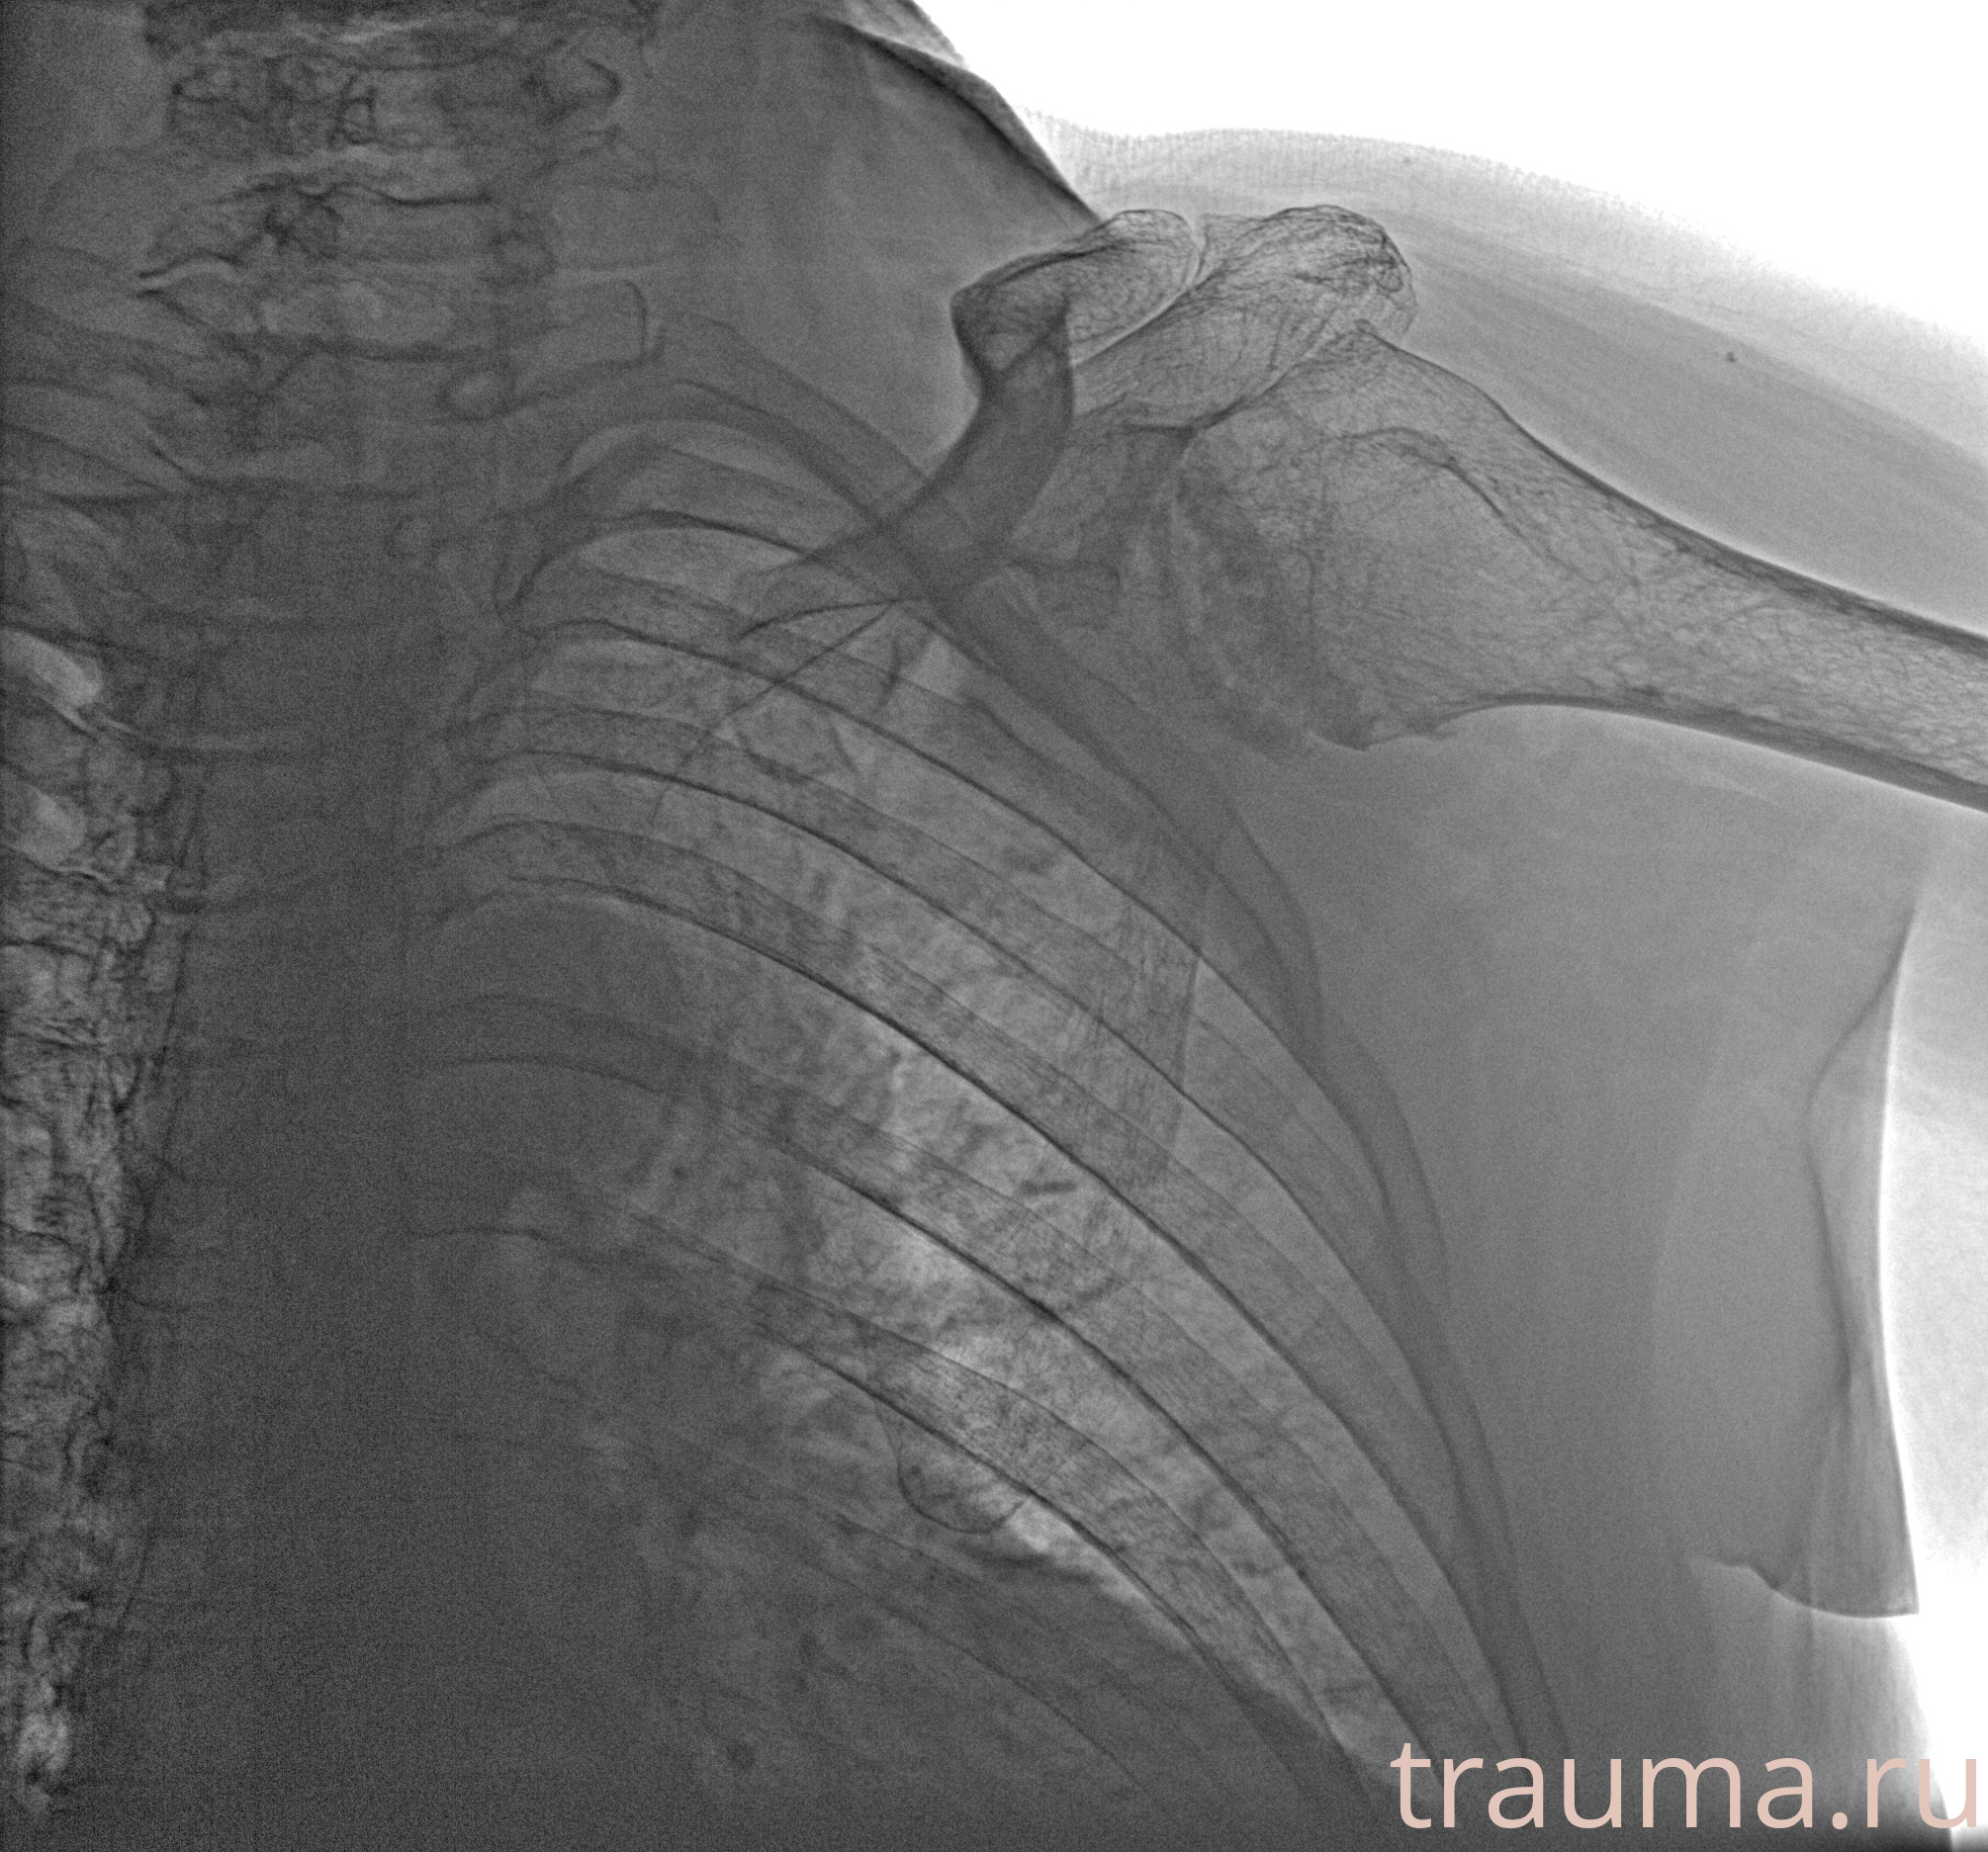

Рентген на дому: по вашему адресу приезжает врач-рентгенолог, травматолог-ортопед с мобильным рентгеновским аппаратом, проводит диагностику травмы или заболевания, делает необходимые рентгенограммы, дает рекомендации по дальнейшему лечению. Получить качественные снимки в домашних условиях возможно благодаря уникальной методике, разработанной МосРентген Центром для института  Склифосовского